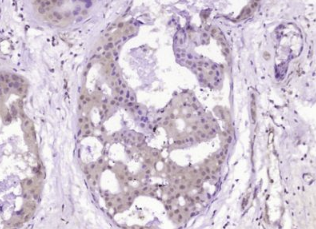

多聚甲醛固定,石蜡包埋(人乳腺癌);经柠檬酸钠缓冲液(pH6.0)煮沸15min后获得抗原;用3%过氧化氢阻断内源性过氧化物酶20分钟;阻断缓冲液(正常山羊血清)37℃30min;用α-肌动蛋白4负荷控制抗体多克隆抗体Unco孵育在4°C温度下,1:400整晚注射,然后根据SP试剂盒(兔子)说明和DAB染色进行操作。